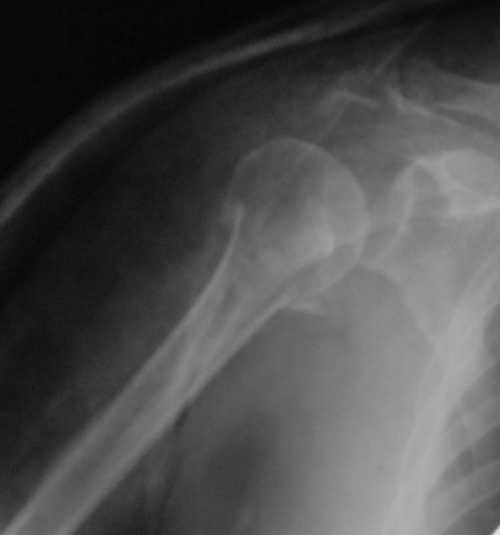

Снимки на 1-е сутки после репозиции и на 8- сутки после репозиции.

Пожалуйста